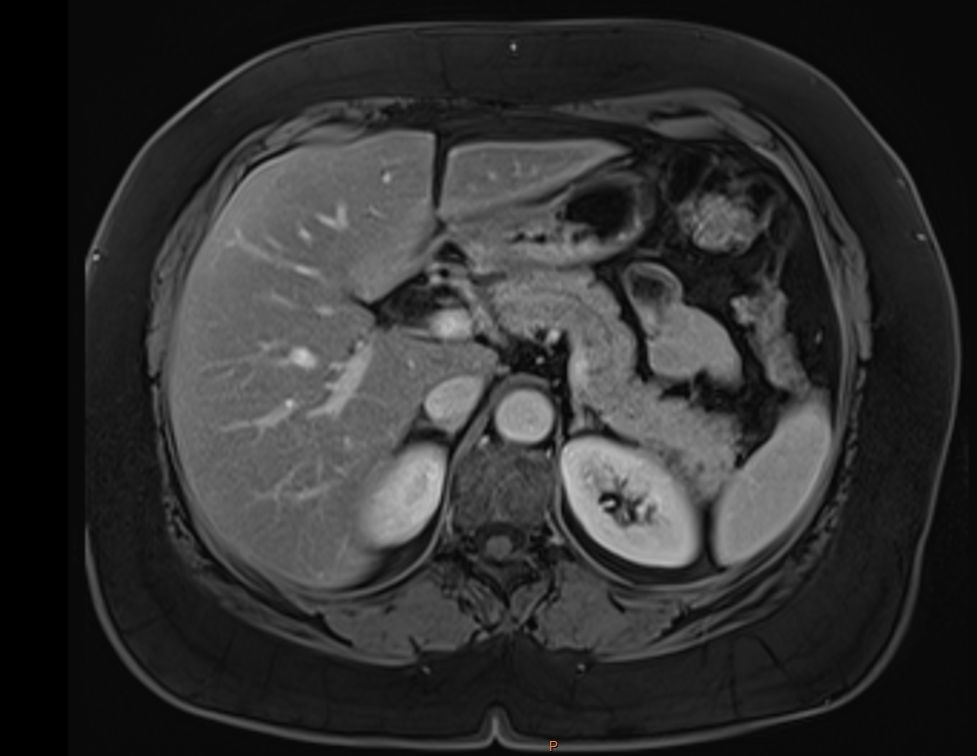

Unveiling Primary Aldosteronism in the Absence of Adrenal Morphological Abnormalities: A Case Report in a Hypertensive Female

Ikram Tahani, Yasmine Ouaddouh, Soumia Boulouiz, Zakaria Bazid, Noha El Ouafi, Nabila Ismaili

A Case Report | 31 Oct 2025

Unveiling Primary Aldosteronism in the Absence of Adrenal Morphological Abnormalities: A Case Report...